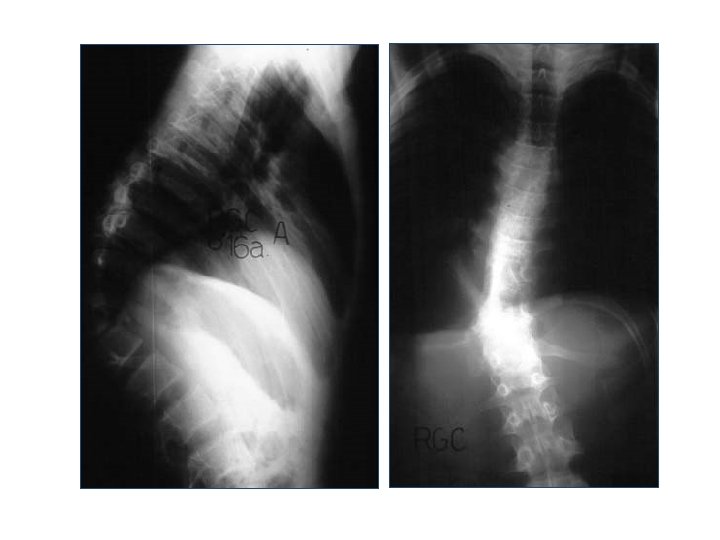

Radiografia

Radiografia Lateral Anteroposterior Alinhamento Altura dos corpos Desvios